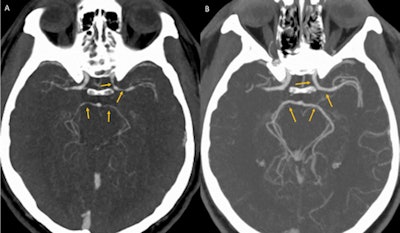

While a urine drug screen and noncontrast head and neck CT scan yielded unremarkable results, CTA (figure A) showed an unexpected multifocal luminal narrowing in the left supraclinoid internal carotid artery, the M1 segment of bilateral middle cerebral arteries, and P1 segments of bilateral posterior cerebral arteries consistent with vasospasm, according to the authors.

A: CT angiography showing unexpected luminal narrowing in the left supraclinoid internal carotid artery, M1 segment of bilateral middle cerebral arteries, and P1 segments of bilateral posterior cerebral arteries consistent with vasospasm. B: CT angiography showing resolution of luminal narrowing after five weeks of supportive care. Images courtesy of BMJ Case Reports 2018."A presumptive diagnosis of thunderclap headache secondary to reversible cerebral vasoconstriction syndrome (RCVS) was made based on the clinical presentation of a severe acute headache, exclusion of aneurysmal subarachnoid hemorrhage, and segmental cerebral arterial vasoconstriction on CT angiography," wrote the authors, led by Dr. Satish Kumar Boddhula of Bassett Medical Center.

While this is the first case of this syndrome that has been reported from chili peppers or cayenne, the authors noted that ingestion of cayenne pepper has been associated with coronary vasospasm and acute myocardial infarction. The patient's symptoms improved with supportive care. He had no further thunderclap headaches, and repeat CTA (figure B) performed five weeks later showed that the luminal narrowing consistent with the syndrome had resolved, according to the authors.